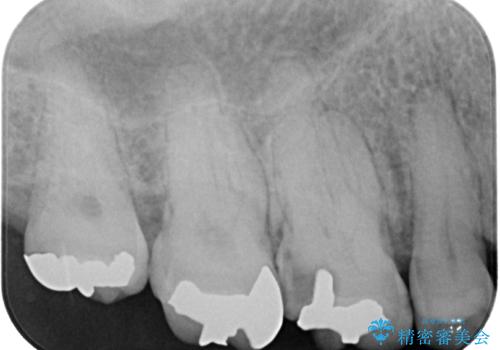

- 奥歯で咬んだときに痛みがあり、物が挟まるとのことで来院された患者様です。

咬み合わせが非常に強く、見た目よりも機能と安定性を重視したいとのことで、PGAクラウン(白金加金合金クラウン)にて補綴する治療計画となりました。